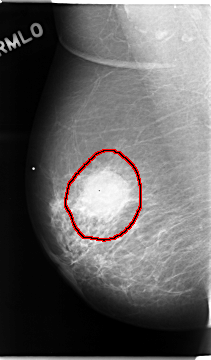

C_0051_1.RIGHT_MLO

RIGHT_MLO LINES 4680 PIXELS_PER_LINE 2736 BITS_PER_PIXEL 12 RESOLUTION 50 OVERLAY

FILE: C_0051_1.RIGHT_MLO.OVERLAY

TOTAL_ABNORMALITIES 1

ABNORMALITY 1

LESION_TYPE MASS SHAPE LOBULATED MARGINS MICROLOBULATED

ASSESSMENT 5

SUBTLETY 5

PATHOLOGY MALIGNANT

TOTAL_OUTLINES 1

BOUNDARY